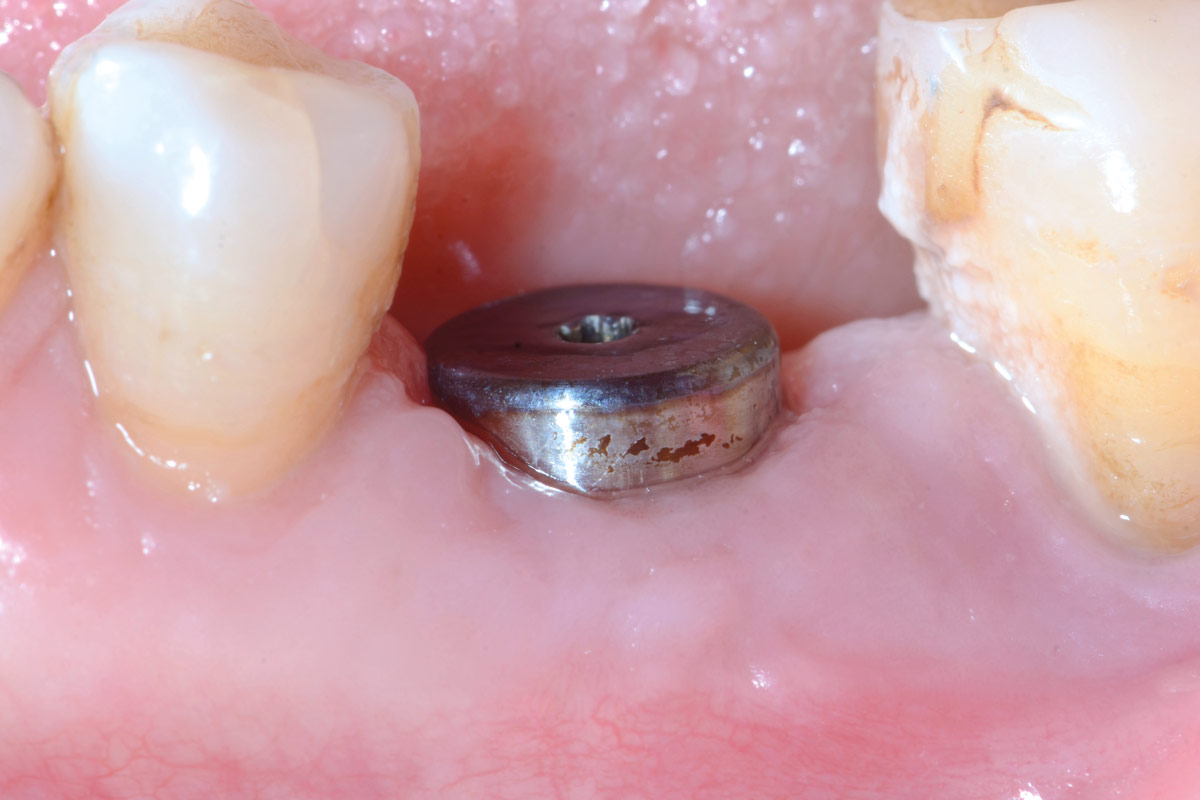

Pre-operative situation showing tooth 21 with deep periodontal pocket. Tooth presented with mobility grade III.